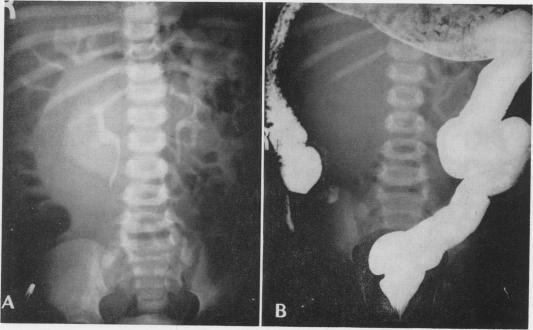

Congenital cysts of the mesentery; report of four cases.

Ann Surg. 1957 Mar;145(3):428-36. doi: 10.1097/00000658-195703000-00020.